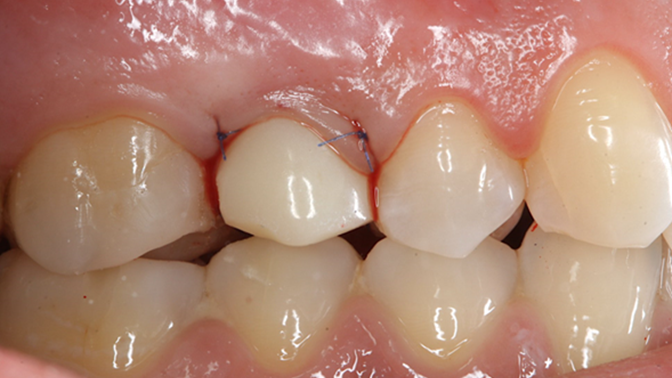

Clinical case: Extraction, immediate implant placement, & provisionalization

- Courtesy of Dr. Iulian Filipov, Romania -

Keywords

AnyRidge, R2GATE, guided surgery, immediate placement, immediate provisionalization, initial stability, Dr. Iulian Filipov, #25, maxillary posterior, immediate loading, Mega ISQ